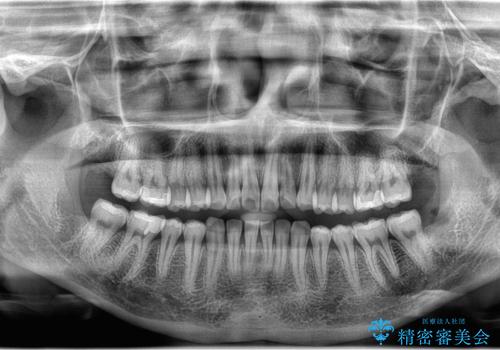

- 下の親知らずは一部分歯肉が被っていたため汚れが溜まりすく、磨き残しにより炎症が生じていました。

抜歯を提案した所希望されたので上下同時に抜歯を行いました。

局所麻酔後に必要に応じて歯肉の切開や、歯を分割して抜歯を行います。

抜歯後は糸で縫って、1週間後に抜糸に来ていただきます。